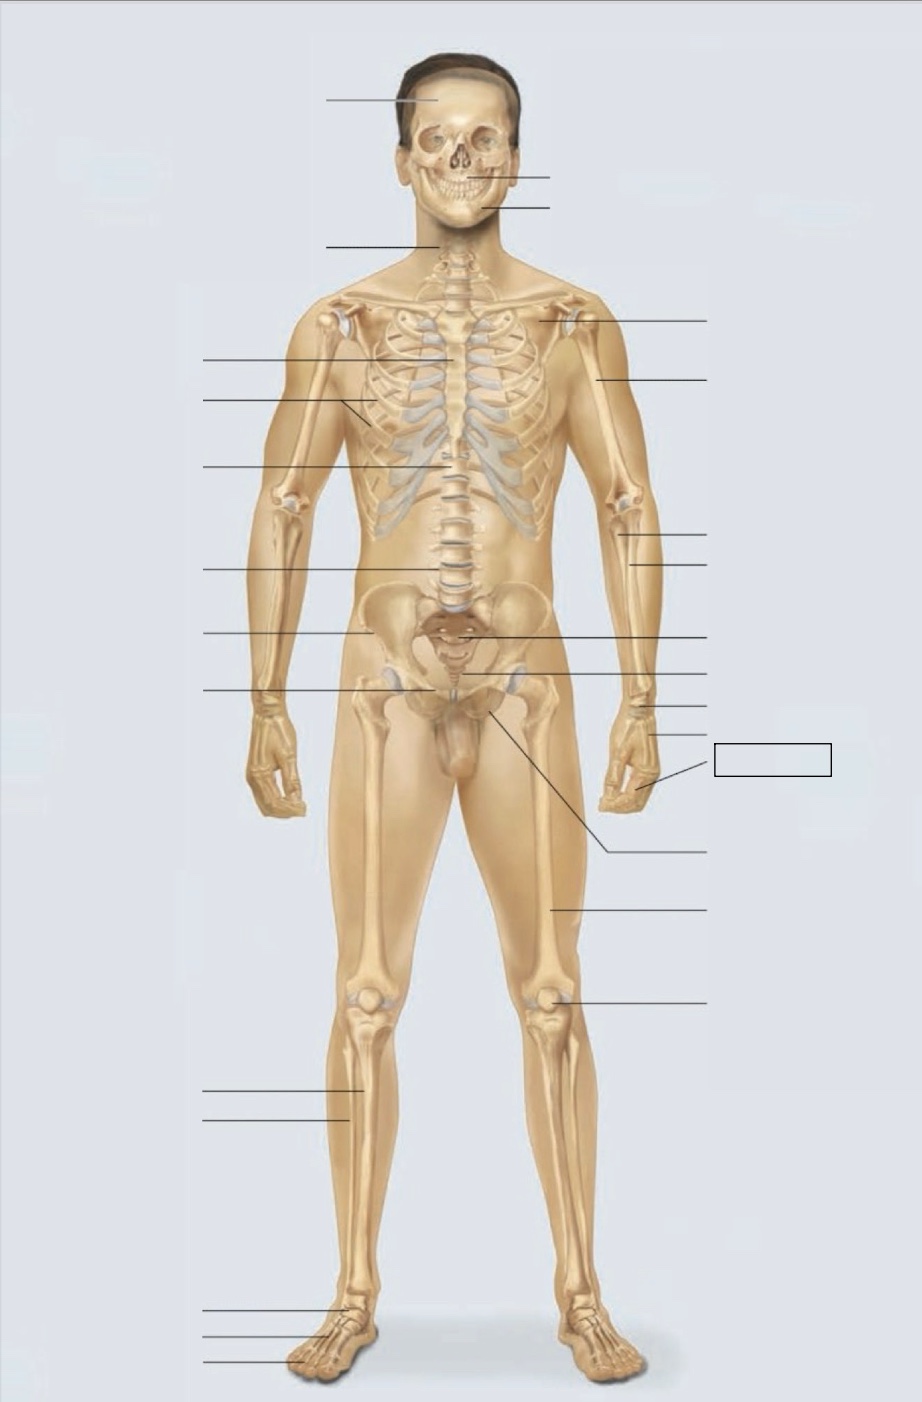

maxilla

mandible

scapula

humerus

ulna

radius

sacrum

coccyx

carpals

metacarpals

phalanges

ischium

femur

patella

phalanges

metatarsals

tarsals

fibula

tibia

pubis

ilium

lumbar vertebrae (L4)

thoracic vertebrae (T11)

ribs

sternum

cervical vertebrae

skull